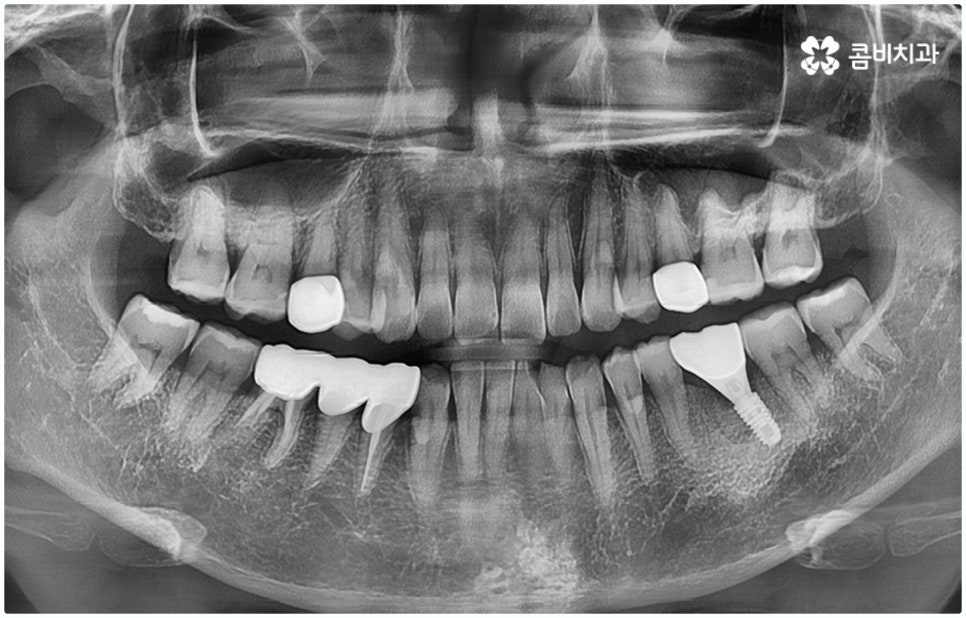

임플란트 시술은 사람의 잇몸뼈와 잘 붙고 인체에 무해한 인공치근(픽스처)을 식립한 후 중간 연결 부분인 지대주와 치아 머리 부분인 크라운을 차례대로 연결하여 기능상 심미상으로 자연 치아를 대체해 주는 인공 치아 식립 방법으로 보통 픽스처를 심을 때 잇몸뼈와 제대로 유착되는 시간이 필요하기 때문에 중간에 일정 시간 회복기를 두고 진행하게 되어 있어요.

이때 환자분들의 상황에 따라 잇몸뼈가 충분하지 않다면 먼저 뼈이식을 통해 이를 단단하게 보충해 주기도 하고, 치주 질환의 치료가 필요하거나 상악동과의 거리가 너무 짧아 거상술이 필요한 경우 이를 선행하기도 하기 때문에 전체 기간은 개개인에 따라 달라질 수 있으며 특히 구강 상태나 연령에 따라 충분한 회복 및 적응 시간을 두지 않으면 식립 성공률이나 장기적인 지속성에 좋지 않은 영향을 줄 수 있으니 주의할 필요가 있습니다.

그렇기 때문에 무조건 보다 빠르고 간편하다고 해서 원데이임플란트 방법을 고집하기 보다는 개인 상태에 따라 필요한 과정을 세심하게 맞춤 진행할 수 있도록 경험이 풍부하고 노하우가 뛰어난 의료진에게 치료 받는 것이 중요한 거예요. 즉 3D CT 등 정밀 검진 장비를 이용하여 환자분들의 치아 및 잇몸 상태, 치아 배열과 교합상태, 주변 치아와의 관계 및 조화까지 꼼꼼하게 파악할 뿐 아니라 턱뼈, 혈관, 신경 등 구강 전체를 함께 분석한 후 체계적인 시술 계획을 세워 각자에 맞는 방법으로 무리하지 않게 수술을 진행할 수 있는 숙련된 의료진과 함께 하는 것이 무엇보다 중요하다고 할 수 있습니다.

또한 잇몸 염증이 없고 치아를 상실한지 오랜 시간이 지나지 않아 남아있는 잇몸뼈가 충분한 분들의 경우와 같이 꼼꼼한 진단 이후 원데이임플란트 수술을 받은 경우라고 해도 사후에 꾸준히 관리해 주지 않으면 임플란트 보철 탈락 및 주위염과 같은 부작용이 생길 수 있으므로 임플란트 수명을 높이기 위해서 치과에서 알려드리는 주의사항을 잘 지키실 필요가 있어요. 또 너무 딱딱하거나 질긴 음식은 피하시고 주기적인 스케일링 치료 및 정기 점검을 받아서 유지 관리에 유념하실 필요가 있습니다